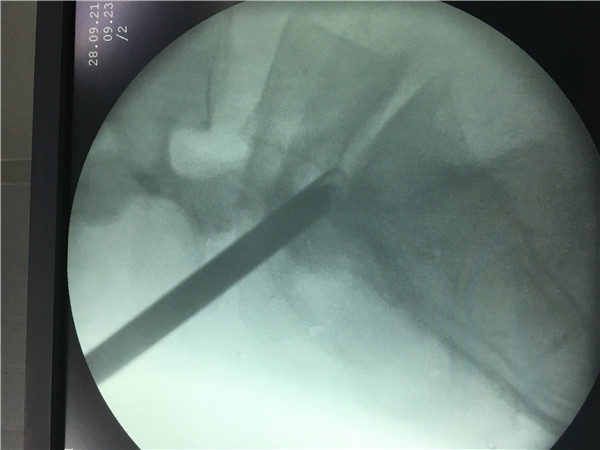

椎间孔镜与脊柱内窥镜类似,是一个配备有灯光的管子,它从病人身体侧方或者侧后方(可以平可以斜的方式)进入椎间孔,在安全工作三角区实施手术。在椎间盘纤维环之外做手术,在内窥镜直视下可以清楚的看到突出的髓核、神经根、硬膜囊和增生的骨组织。然后使用各类抓钳摘除突出组织、镜下去除骨质、射频电极修复破损纤维环。